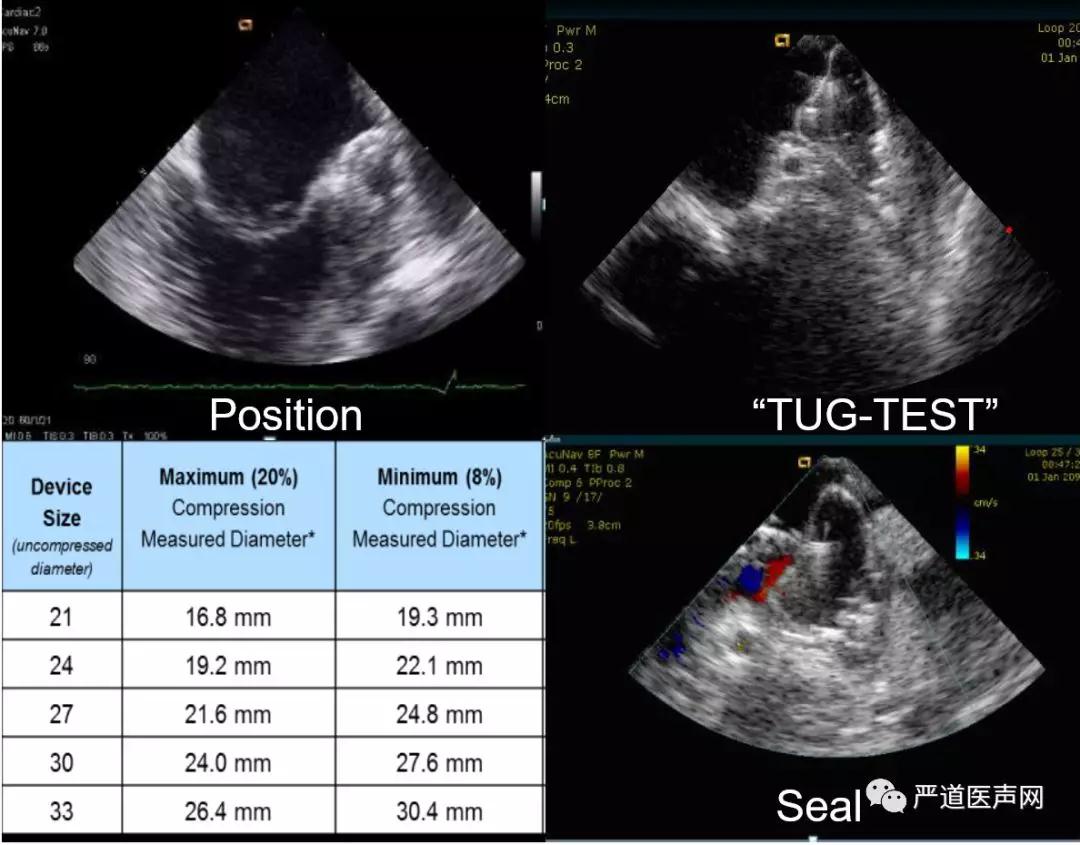

图9 与TEE相匹配的ICE视野观察左心耳结构

第七步,封堵器装置释放前检验。这里以塞式封堵器WATCHMAN为例,查看封堵器释放位置、牵拉试验、封堵器压缩比测定、封堵器残余分流测定。释放前符合位置、锚定、尺寸、密封的PASS原则(此处不再赘述)。需要注意的是,彩色多普勒评估残余分流时,视野囊括封堵器平面左心耳壁的前提下,确认多个角度下可以重复的色彩带分流(不一定是最小的),选取最窄处测量宽度;牵拉试验既可以在右房间隔侧观察也可以穿间隔至左房在LSPV后上侧观察,塞式封堵器在应用ICE时,超声不会受封堵盘的遮挡,视野更清晰,盘式封堵器因其封堵盘或遮挡超声视野,需要更注意观察心耳同步运动。

图10 封堵器释放前确认PASS原则(以塞式封堵器为例)